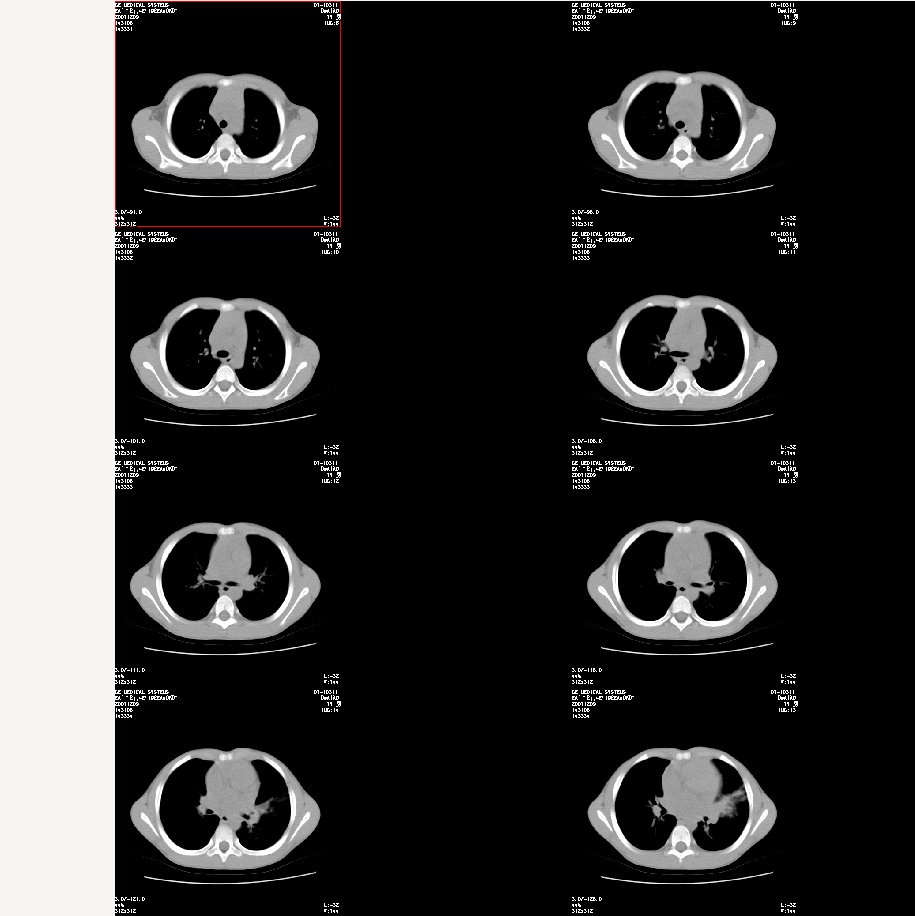

标题: 纵隔窗: